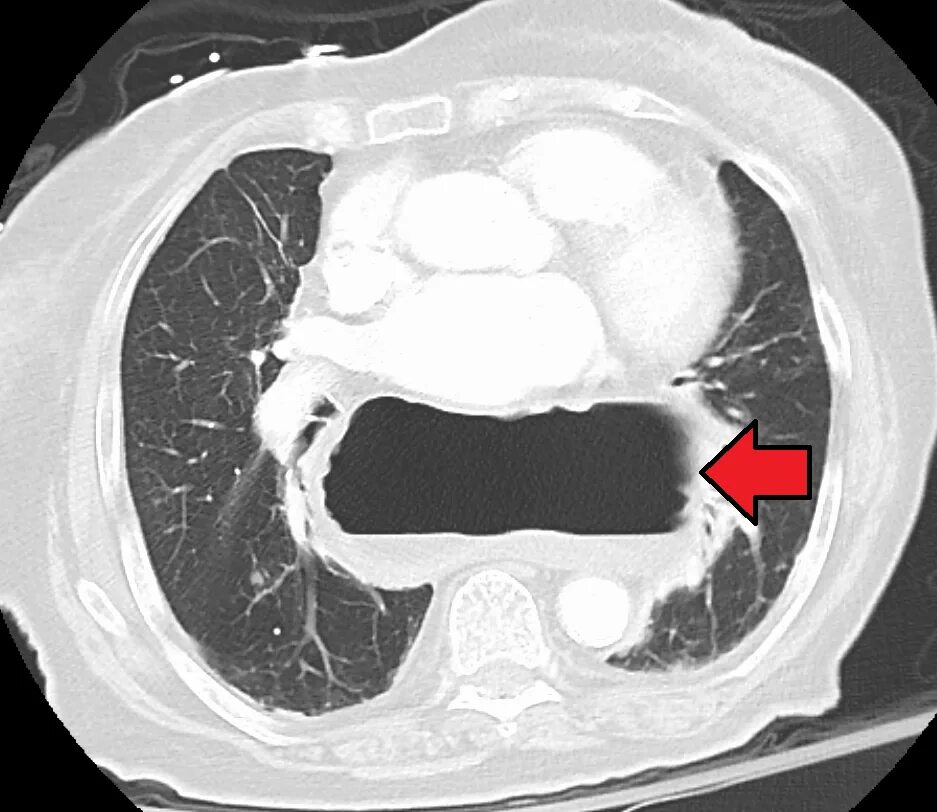

Грыжи на кт